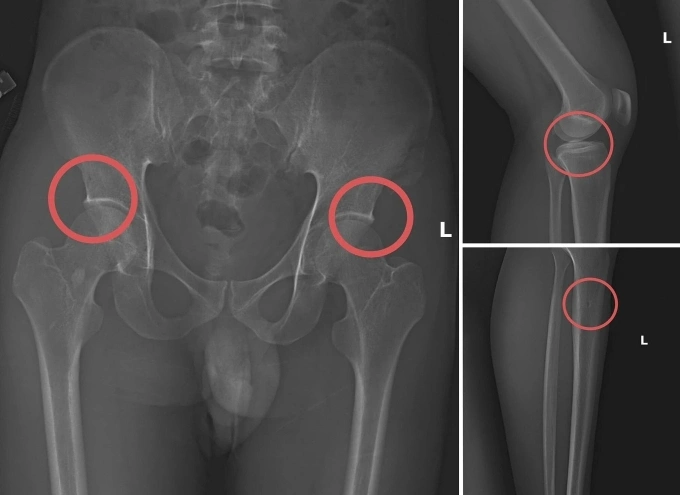

Phú Thọ- Tạ Minh Châu, nguyên cán bộ y tế, đã cho người mua bảo hiểm nhân thọ giá trị cao, rồi tiêm thuốc mê, dùng búa đinh đục gãy xương chậu, đùi của họ để cùng trục lợi tiền.